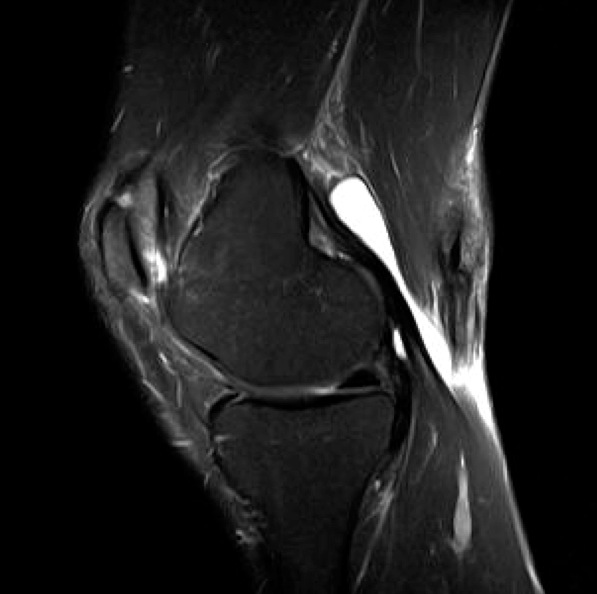

Figure 1 for case Hematoma

Figure 1

Discussion

Semitendinous muscle tear with hematoma

Diagnosis

Hematoma